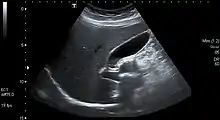

Gallstones form when the bile is saturated, usually with either cholesterol or bilirubin.[20] Most gallstones do not cause symptoms, with stones either remaining in the gallbladder or passed along the biliary system.[21] When symptoms occur, severe "colicky" pain in the upper right part of the abdomen is often felt.[20] If the stone blocks the gallbladder, inflammation known as cholecystitis may result. If the stone lodges in the biliary system, jaundice may occur; if the stone blocks the pancreatic duct, pancreatitis may occur.[21] Gallstones are diagnosed using ultrasound.[20] When a symptomatic gallstone occurs, it is often managed by waiting for it to be passed naturally.[21] Given the likelihood of recurrent gallstones, surgery to remove the gallbladder is often considered.[21] Some medication, such as ursodeoxycholic acid, may be used; lithotripsy, a non-invasive mechanical procedure used to break down the stones, may also be used.[21]

An ultrasound is often the first medical imaging test performed when gallbladder disease such as gallstones are suspected.[21] An abdominal X-ray or CT scan is another form of imaging that may be used to examine the gallbladder and surrounding organs.[21] Other imaging options include MRCP (magnetic resonance cholangiopancreatography), ERCP and percutaneous or intraoperative cholangiography.[21] A cholescintigraphy scan is a nuclear imaging procedure used to assess the condition of the gallbladder.[28]